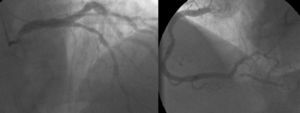

A coronariografia (Figura 2) revelou doença coronária de 2 vasos (lesão de 75% no segmento médio da descendente anterior e lesão de 90% na origem da descendente posterior). O estudo hemodinâmico determinou um gradiente transvalvular aórtico de 97mmHg.

Atendendo ao quadro de instabilidade hemodinâmica com choque cardiogénico, foi decidida a realização de valvuloplastia aórtica (Figura 3) com balão NUCLEUS 20mm, sob ritmo de pacing a 220 bpm, verificando-se uma redução do gradiente de 97 para 46mmHg. Ao mesmo tempo, foi feita revascularização miocárdica completa com colocação de dois stents sem fármaco. A aortografia revelou insuficiência aórtica moderada, pelo que se optou pela não colocação de balão intra-aórtico.